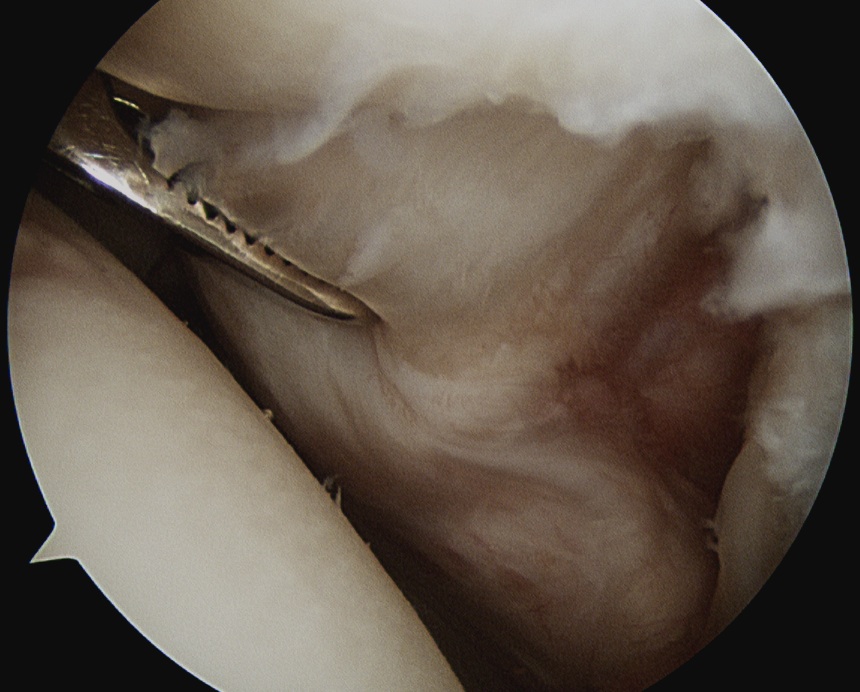

Prepare footprint

- debride

- insert anchors (retract port of Wilminton into subacromial space)

- pass sutures with suture passer

- tie